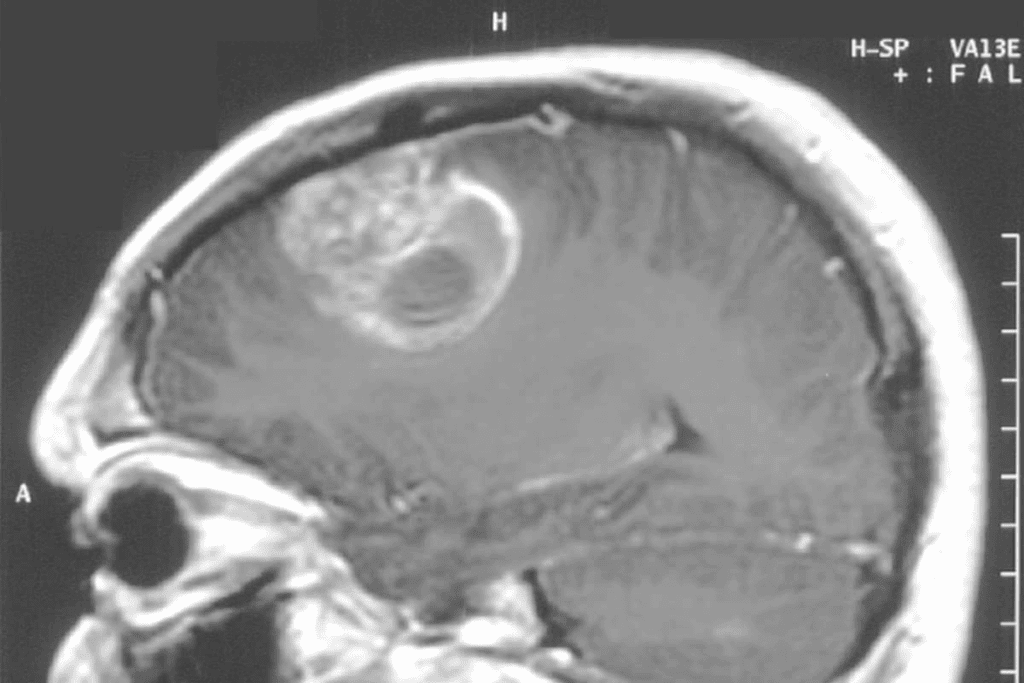

Imaging Characteristics of DIPG

Diagnosing DIPG uses advanced imaging like MRI. DIPG tumors look like diffuse, infiltrative lesions in the pons. They often spread into the surrounding brainstem structures.

This makes it hard to plan surgery. MRI sequences like diffusion-weighted imaging and MR spectroscopy help. But, DIPG’s growth into the brainstem tissue is a big challenge for surgery.